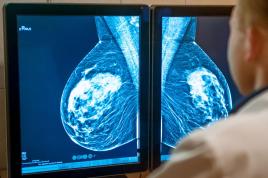

تراکم پستان در دوران نوجوانی تحت تاثیر هورمونها شکل میگیرد و یک شاخص مهم خطر سرطان پستان است

سرطان پستان